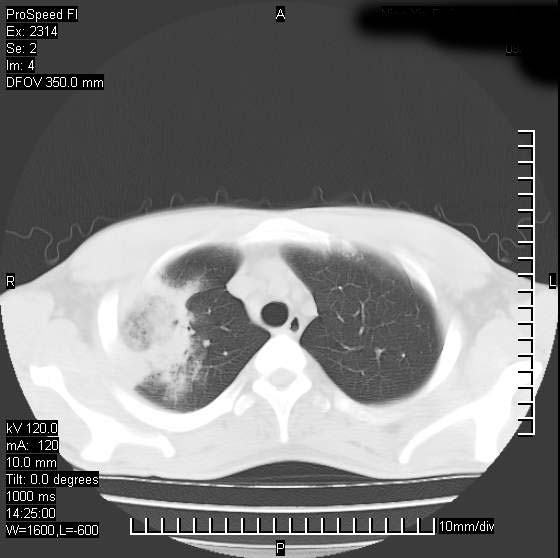

男性,再生障碍性贫血,入院前发热10天,最高40c,右侧胸痛,外院ct示右上,中肺边缘模糊的球性影(就是我现在图中标示的范围),考虑炎症,在我院使用头孢呋辛,洛美沙星10天,高烧消退,自感下午稍有发热,但今天ct示右上,中肺病灶明显扩大,还是考虑炎症,看其中的球型影是否霉菌感染??,是否能排除结核?

右肺中叶外侧段病变,上缘界限不清,下缘锐利,以段性发病为主,内见巨大空洞及空洞内容物,结合病史首先考虑:化脓性肺炎。不除外霉菌感染!

片状高密度影内见空洞影,内可见球形软组织密度影,并有新月征,考虑霉菌感染.